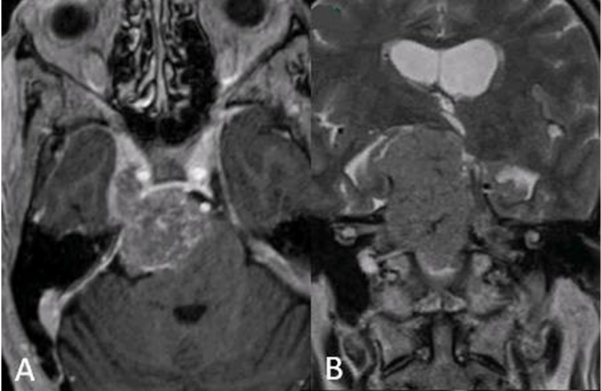

70岁女性、岩斜区脑膜瘤,脸部剧痛,伴幕上侵犯,可见脑干受压现象,肿瘤延伸至梅克尔腔(Meckel’s cave)及右侧海绵窦。

福教授采用了微型联合岩骨入路(mini-CTPA),成功实现了肿瘤的近全切除。点击阅读:【福医妙手】INC国际教授福洛里希脑膜瘤案例九|70岁,岩斜区脑膜瘤,近全切